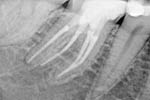

Revisionsbehandlung eines Unterkiefermolaren (37) vor geplanter Überkronung (Dr. Maik Göbbels) Download